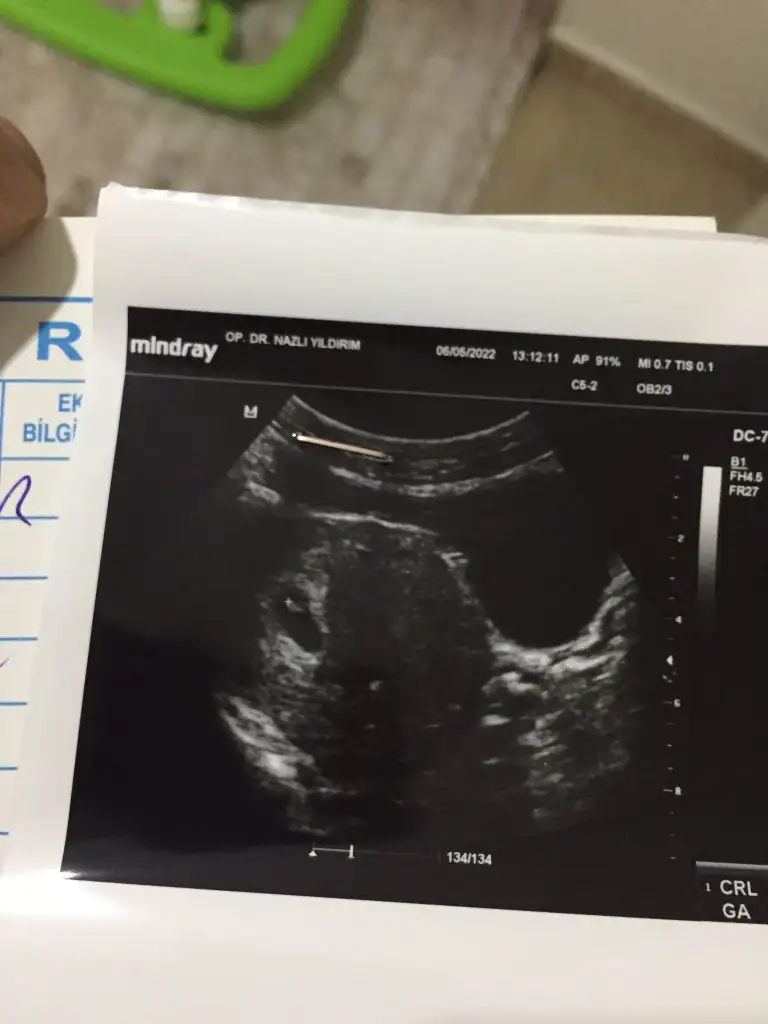

Canım benim fotoğrafımı da yorumlar mısın 7 hafta karındanben kız olarak yorumladım ama bu de sen bak